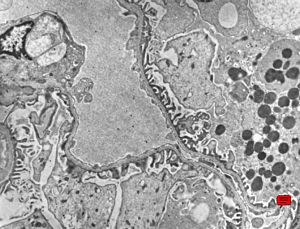

M,67y. | normal kidney

F,49y. | normal kidney

M,34y. | normal kidney